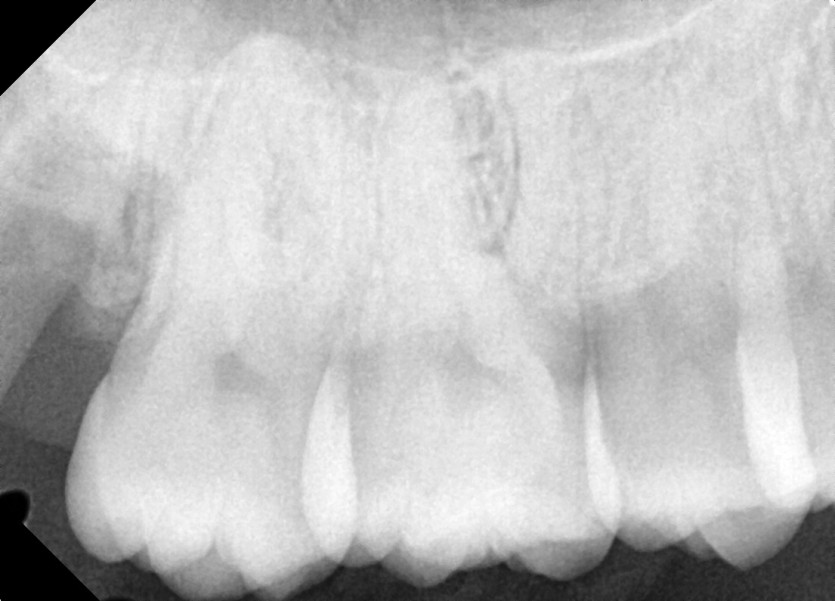

#18,28,48 사랑니 발치

구강 외과 전문의가 당일 발치했습니다.